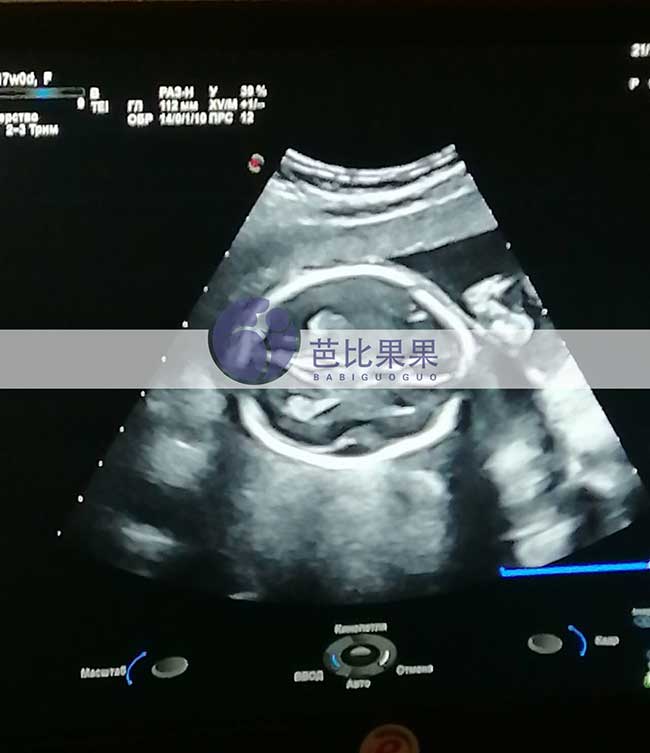

J先生的乌克兰试管妈妈按时基辅妇产医院做孕17周B超孕检

J先生家乌克兰试管妈妈按时到我们熟悉的基辅妇产医院做孕17周B超孕检,胎儿发育得很好,孕妈身体状态也很好,辛苦她了